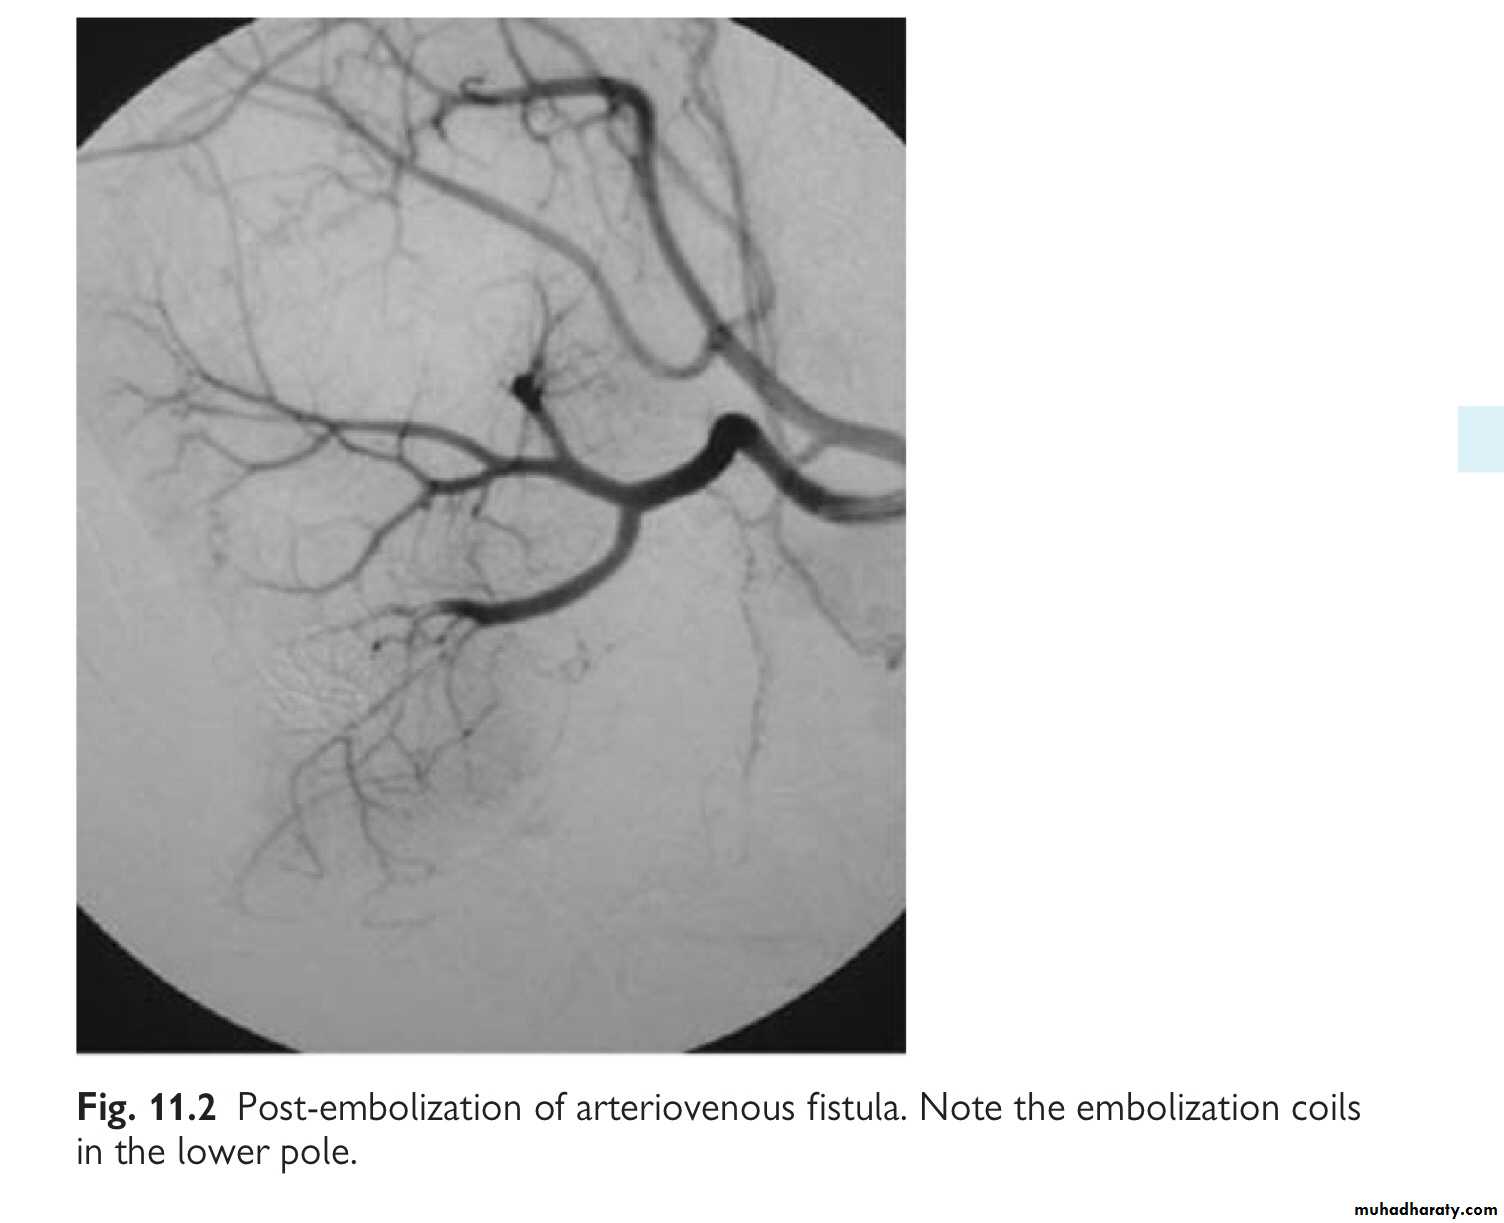

Ureteric injuries: mechanisms and diagnosis

- External: rare—blunt (e.g. high-speed road traffic accidents, fall from a height; penetrating (knife or gunshot wounds). –

Internal trauma (= iatrogenic): during pelvic or abdominal surgery, e.g. hysterectomy, colectomy, AAA repair; ureteroscopy. The ureter may be divided, ligated, or angulated by a suture; a segment excised or damaged by diathermy.